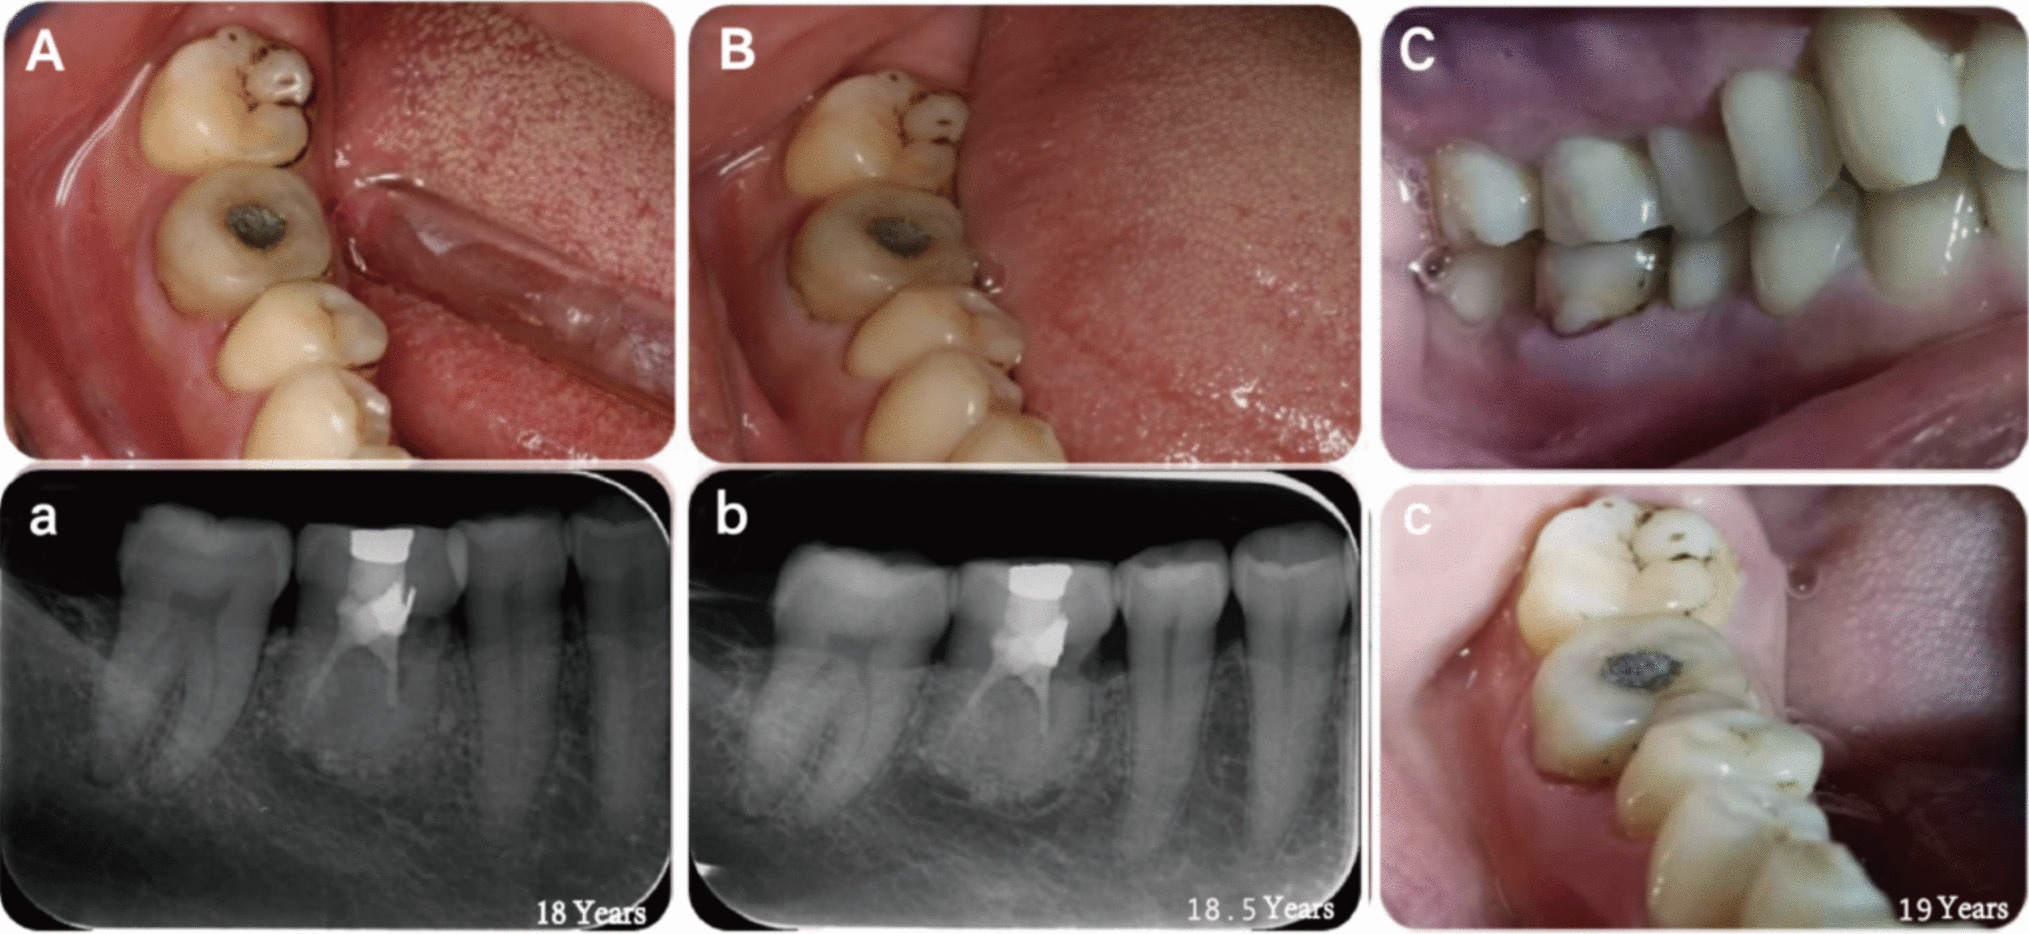

18 years later, we fortuitously reconnected with the patient and conducted a comprehensive examination. During this visit, the patient reported experiencing pulpitis resulting from caries in the tooth, prompting orthograde endodontic treatment. Intraoral examination revealed that tooth 46 was discolored and filled with silver amalgam. The gingiva exhibited no redness or swelling, and there was no percussion pain (Fig. 13).

Fig. 13

A eighteen years postoperative (intraoral photograph) (a) eighteen years postoperative (satisfactory periodontal healing) (B) eighteen and a half years postoperative (intraoral photograph) (b) eighteen and a half years postoperative (normal ligament gaps) (C) nineteen years postoperative (adequate centric occlusal contact position) (c) nineteen years postoperative (intraoral photograph)

Bild vergrößern